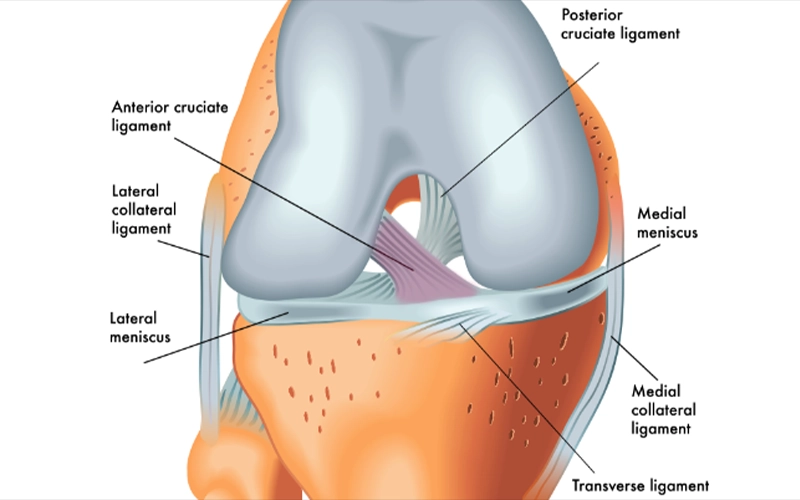

منیسک داخلی زانو ساختاری به شکل حرف C باز دارد و شعاع انحنای آن از منیسک خارجی بیشتر است. منیسک داخلی زانو دارای دو بخش به نام شاخ قدامی و شاخ خلفی است.

شاخ خلفی منیسک داخلی پهنتر از شاخ قدامی بوده و در قسمت جلویی رباط صلیبی خلفی (PCL) به استخوان تیبیا متصل میشود. شاخ قدامی نیز در فاصله حدود ۶ تا ۸ میلیمتر جلوتر از رباط صلیبی قدامی (ACL) به تیبیا اتصال دارد.

قسمت محیطی منیسک داخلی به کپسول داخلی مفصل زانو متصل است و این اتصال از طریق لیگامان کورونری به لبه فوقانی استخوان تیبیا انجام میشود.

منیسک خارجی شکلی نزدیک به C بسته دارد و شعاع آن کمتر از منیسک داخلی است. این منیسک نسبت به نوع داخلی، سطح وسیعتری از بخش فوقانی استخوان تیبیا را میپوشاند.

منیسک خارجی از اطراف به کپسول مفصلی خارجی زانو متصل است. شاخ قدامی آن به ناحیه جلویی برجستگیهای بینکندیلی متصل میشود و شاخ خلفی نیز در قسمت خلفی همین برجستگیها و در جلوی محل اتصال شاخ خلفی منیسک داخلی قرار دارد.